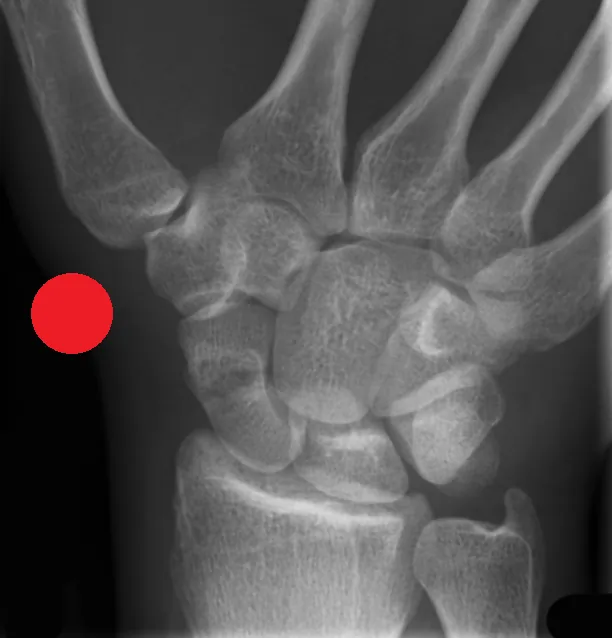

Red Dot Course for Radiographers (Online)